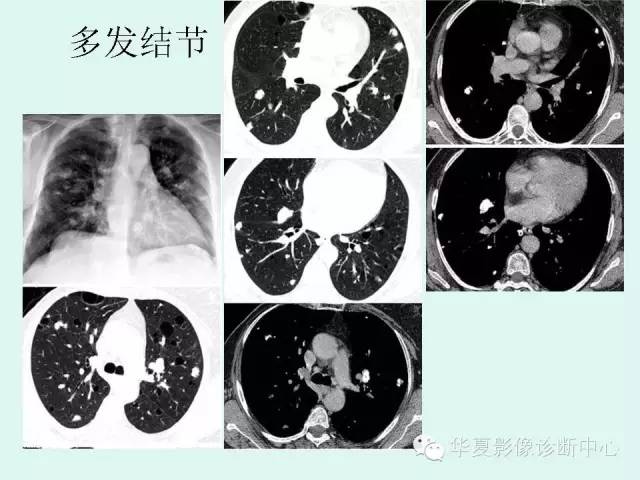

肺淀粉样变性1例CT影像表现

【病例】肺淀粉样变性1例CT影像表现